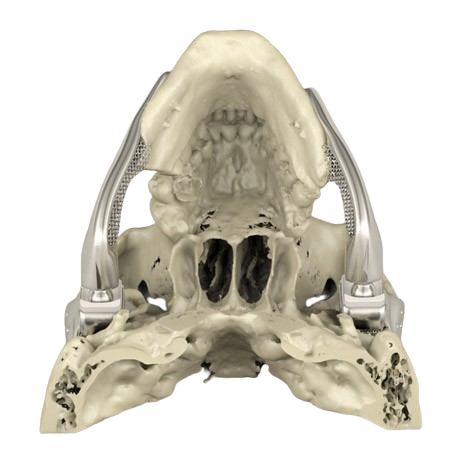

Custom anatomical models

High-quality anatomical models are expensive and offer a finite set of options for the best. The templates are routinely used by students and professionals for education, training, surgical planning, and visual aids for patients.

With affordable 3D printing services, medical professionals and educators can create customized anatomical models at a low cost for various purposes. For example, surgeons can perform complex procedures using patient-specific models that accurately simulate the situations they may face during surgery.